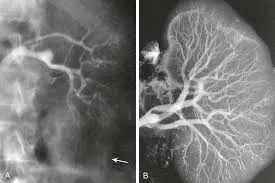

A DRPAD não é contraindicação à DP — e, na prática, muitos pacientes têm resultados comparáveis à hemodiálise. O “porém” está na mecânica: rins/hepatomegalia podem reduzir tolerância a volumes, aumentar risco de hérnias e extravasamentos, e piorar desconforto respiratório. Com técnica adequada (cateter presternal ou lateral, volumes menores, cicladora noturna e decúbito supino), a maioria das barreiras é contornável. Neste post, revisamos quando a DP é ótima, quando exigir cautela e como ajustar a prescrição para segurança e qualidade de vida.